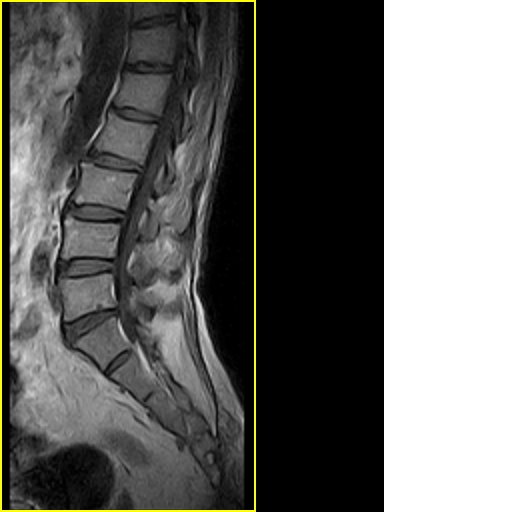

男,78岁,右下肢跛行两月.

腰间盘膨出、黄韧带肥厚、可疑先天性腰椎管狭窄。

退行性骨关节病:增生、椎间盘变性、膨出...

退行性病变:增生、椎间盘变性、膨出[l4-5、l5-s1 椎间盘膨出]

退行性骨关节病:增生、椎间盘变性、膨出..黄韧带肥厚.